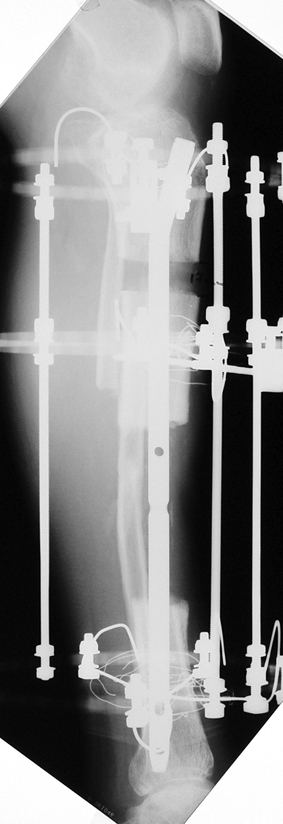

Appropriate radical debridement necessitates excision of all necrotic bone and soft tissues, and frequently causes instability at the involved extremity. The remaining bone and soft tissue defect has to be fixed and reconstructed. The distraction osteogenesis method of Ilizarov is used successfully for achievement of union, correction of the deformity, elimination of limb length inequality and reconstruction of segmental bone defects.

The duration of external fixation (external fixation index) depends on the amount of distraction required, and the extremity is prone to complications during this period. After the distraction phase is completed, the external fixator remains in place during the consolidation phase, which lasts twice as long as the distraction phase; but this period is hardly tolerated. If the external fixator is removed before sufficient consolidation is achieved, fractures, deformity and shortness will be the result. In our department, ‘lenghthening over nail’ method is used in order to decrease the external fixation index and increase patient comfort and activity level. In this method, the intramedullary nail is statically locked after the completion of the distraction phase, and external fixator is removed. The extremity is stabilized by the intramedullary nail during consolidation phase. In this way, complications due to long external fixation index or early removal of the external fixator are avoided.

Case 2